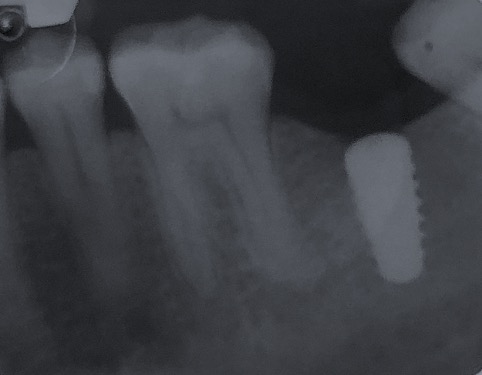

Un impianto dentale o fixture è un corpo in titanio, totalmente biocompatibile, che viene posizionato nella mascella o mandibola con lo scopo di sostituire la radice di un dente naturale perso. Su di esso viene successivamente o immediatamente quando possibile (carico immediato) fissata la protesi ovvero la corona del dente restituendo funzione ed estetica.

Gli impianti non hanno scadenza quindi non sono un rimedio temporaneo ma una soluzione definitiva per tornare ad avere denti come quelli originali. L’osteointegrazione è così forte e perfetta che se volessimo rimuovere l’impianto in un secondo momento dovremmo togliere anche l’osso che lo circonda.

Nulla è per sempre, come anche i denti naturali. Un impianto può andar incontro ad una perimplantite, infiammazione che attacca il tessuto osseo circostante fino a causarne la mobilità. I fattori che predispongono alla perdita di un impianto sono: fumo di sigaretta, scarsa igiene orale, sovraccarico meccanico, predisposizione genetica. Le cause certe non sono ancora del tutto note al giorno d’oggi.

Qualità degli impianti e tipo di trattamento di superficie, caratteristiche nel design della protesi e corretto posizionamento sono fattori fondamentali per ridurre il rischio di perdere un impianto.